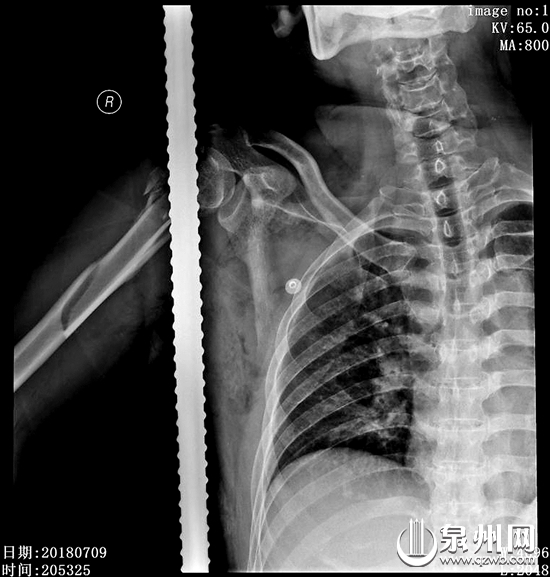

钢筋直接从叶师傅身体中穿过(解放军第180医院供图)

此时,医院也紧急为患者开通绿色通道,由骨一科19病区承担救治工作,科主任尤瑞金组织医生一起对患者的病情进行讨论,快速拟订手术方案。叶师傅术前X片及CT显示,钢筋已将肱骨头完全击穿,巨大的外力造成肱骨头及肱骨上段粉碎性骨折,骨头碎片散布在周围组织中,术中必须保护固定好关节及骨头,并尽可能将骨头碎片取出。